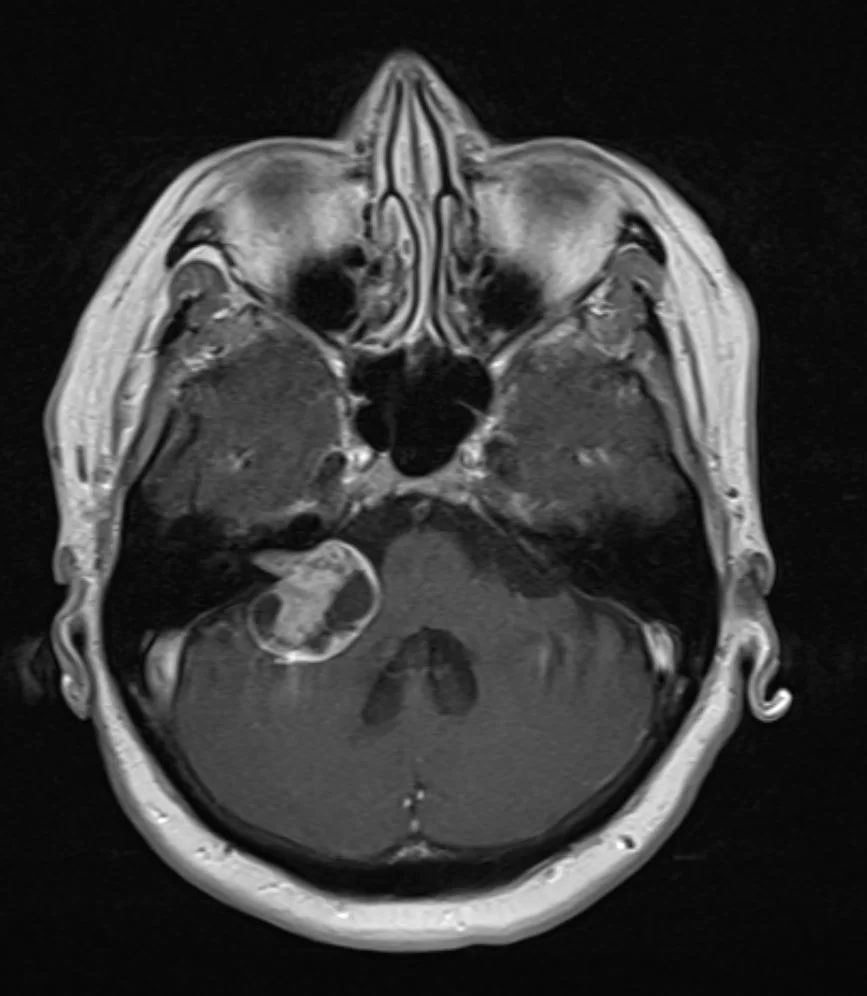

Αφαίρεση Μηνιγγιώματος Κορυφής Λιθοειδούς

Ασθενής 53 ετών η οποία από πολλά χρόνια παραπονιόνταν για νευραλγία τριδύμου, δηλαδή πόνο στην περιοχή του προσώπου, κυρίως στην περιοχή της άνω και κάτω